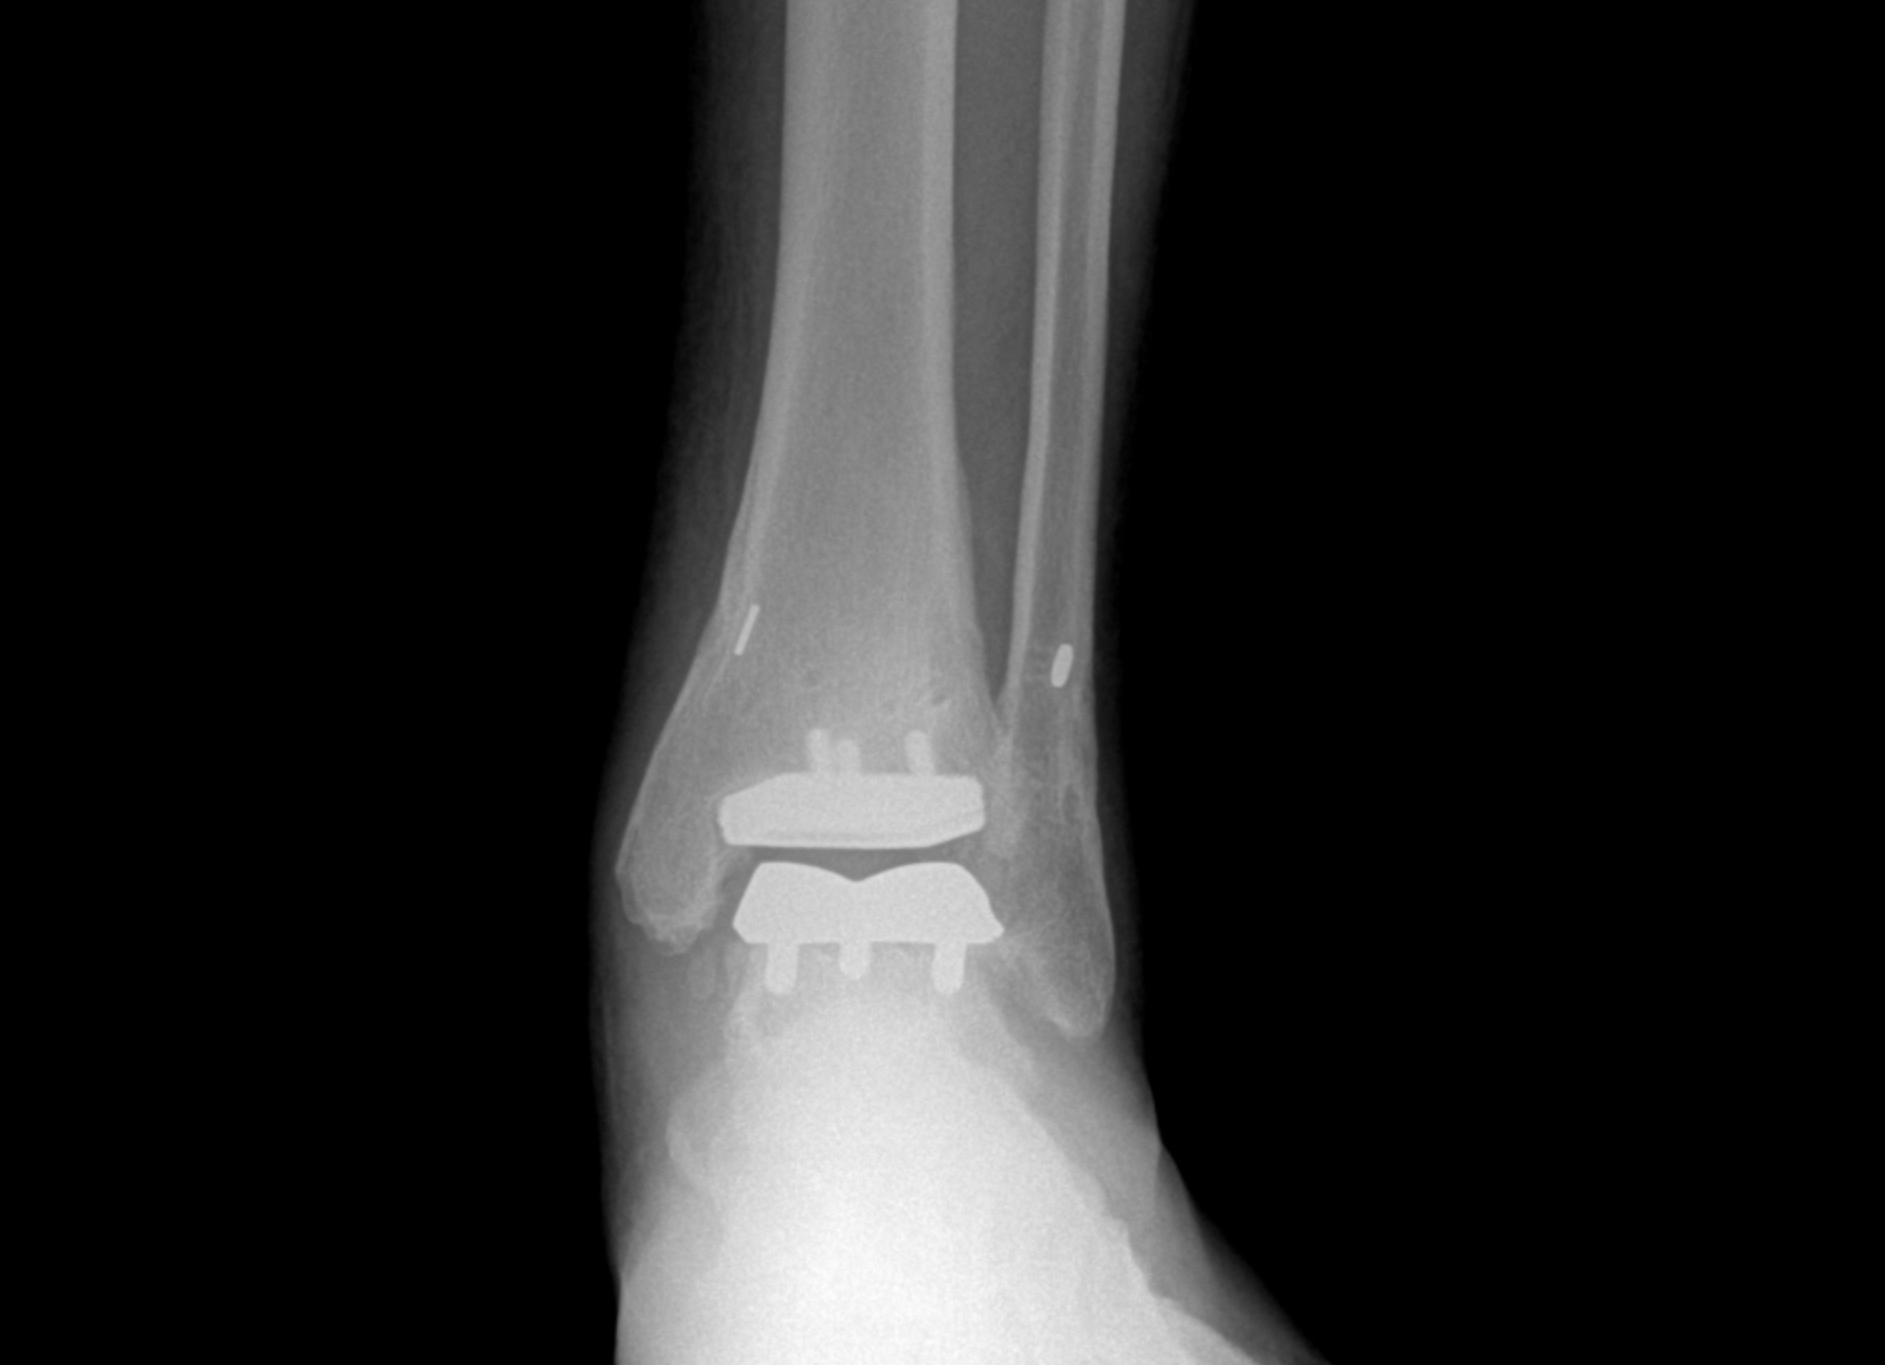

Foot & Ankle Replacement

Coming Soon